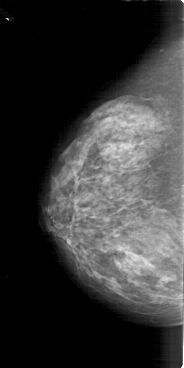

A_1664_1.RIGHT_CC

RIGHT_CC LINES 6586 PIXELS_PER_LINE 3346 BITS_PER_PIXEL 12 RESOLUTION 43.5 OVERLAY